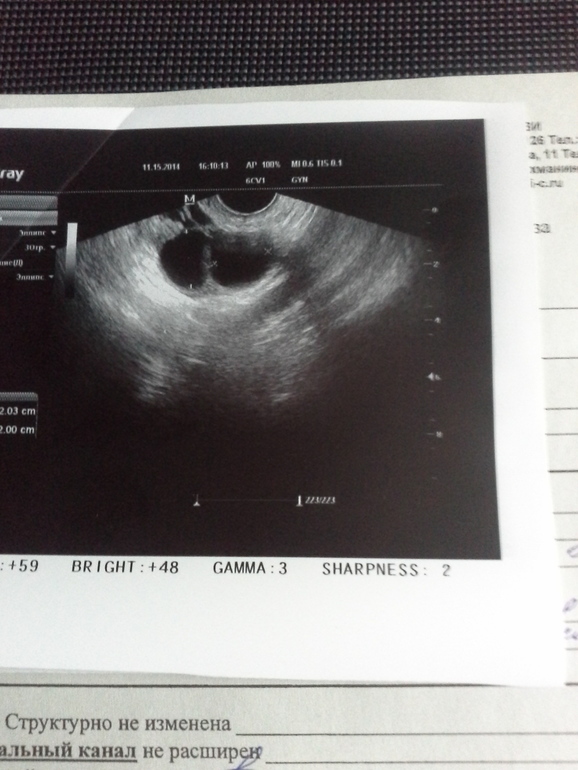

В ПЯ уже 3 цикла сидела сначала 1 функциональная киста,потом 2, потом опять 1. Из-за этого не могу вступить в протокол((((. В этом цикле, на 2ДЦ, киста уменьшилась,но оставалась на месте(((. Проставила Индометацин по очереди с Лонгидазой 5+5шт, пью Вобъэнзим и прохожу курс пиявочек))). Надежда вступить в протокол в первых числах декабря... Вчера сходила на УЗИ, 12 ДЦ:

Врач сказала, что это больше на ДФ похоже. Ну один-то точно ДФ пока, т.к. он единственный был виден рядом с кистой на 2ДЦ и был 5мм. А второй новый фоллик или киста всё ещё сидит?!

Мариш,привет!Долго рассматривала,но так и не поняла-кисты это или дф или один дф и одна киста(((Думаю,чтобы точно узнать-сходи дней через пять на узи,если дф,то лопнет уже и будет видна жидкость за маткой и жт.А пока не ясно.

Собираюсь во вторник на УЗИ)))Дело в том, что на 2ДЦ была одна киста, думаю, что за 10 дней фоллик из 5мм в 20мм только в ДФ вырасти может. Так что 1, походу, точно ДФ. Жду, что лопнет)))

А ХЗ? В заключении, на первой фотке,написала: "доминантные фолликулы? киста правого яичника?" Мне кажется больше левый похож. Чё, думаешь, это обе кисты??